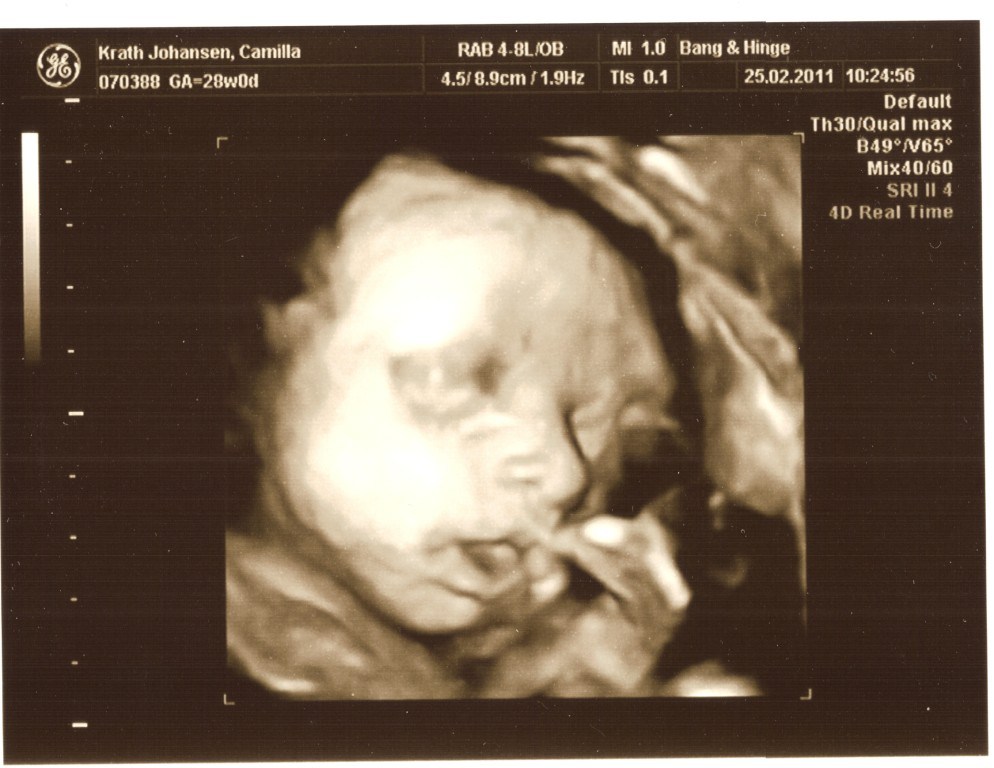

Jeg gjorde det i uge 30, og jeg vil IKKE anbefale at gøre det senere.

Selvom vores søn var lille, så havde han ikke meget plads at ligge på i uge 30, og da de ligger "lidt klemt", så blir det sværere at se noget, jeg større de blir. Vi fik nogen rigtig gode billeder, men det tog en del tid, fordi hans arme lå presset op foran hans ansigt og det er jo svært lige at flytte dem

Men sikke en stor oplevelse